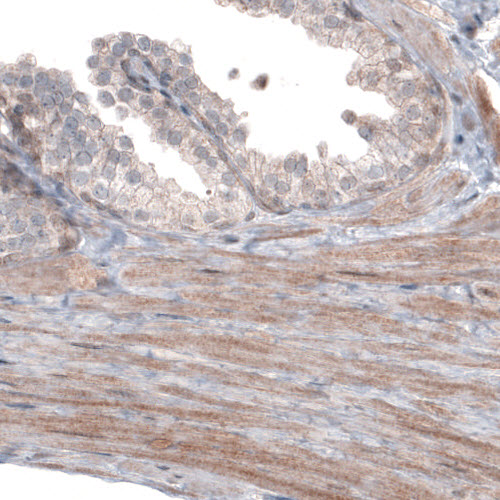

Immunohistochemical staining of human skeletal muscle shows moderate cytoplasmic immunoreactivity in muscle fibers.